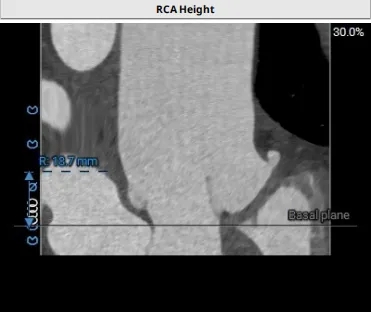

冠脉风险评估

Left Coronary 8.0mm

Right Coronary 18.7mm

左冠开口较低,结合瓦氏窦大小,预估冠脉风险相对较低